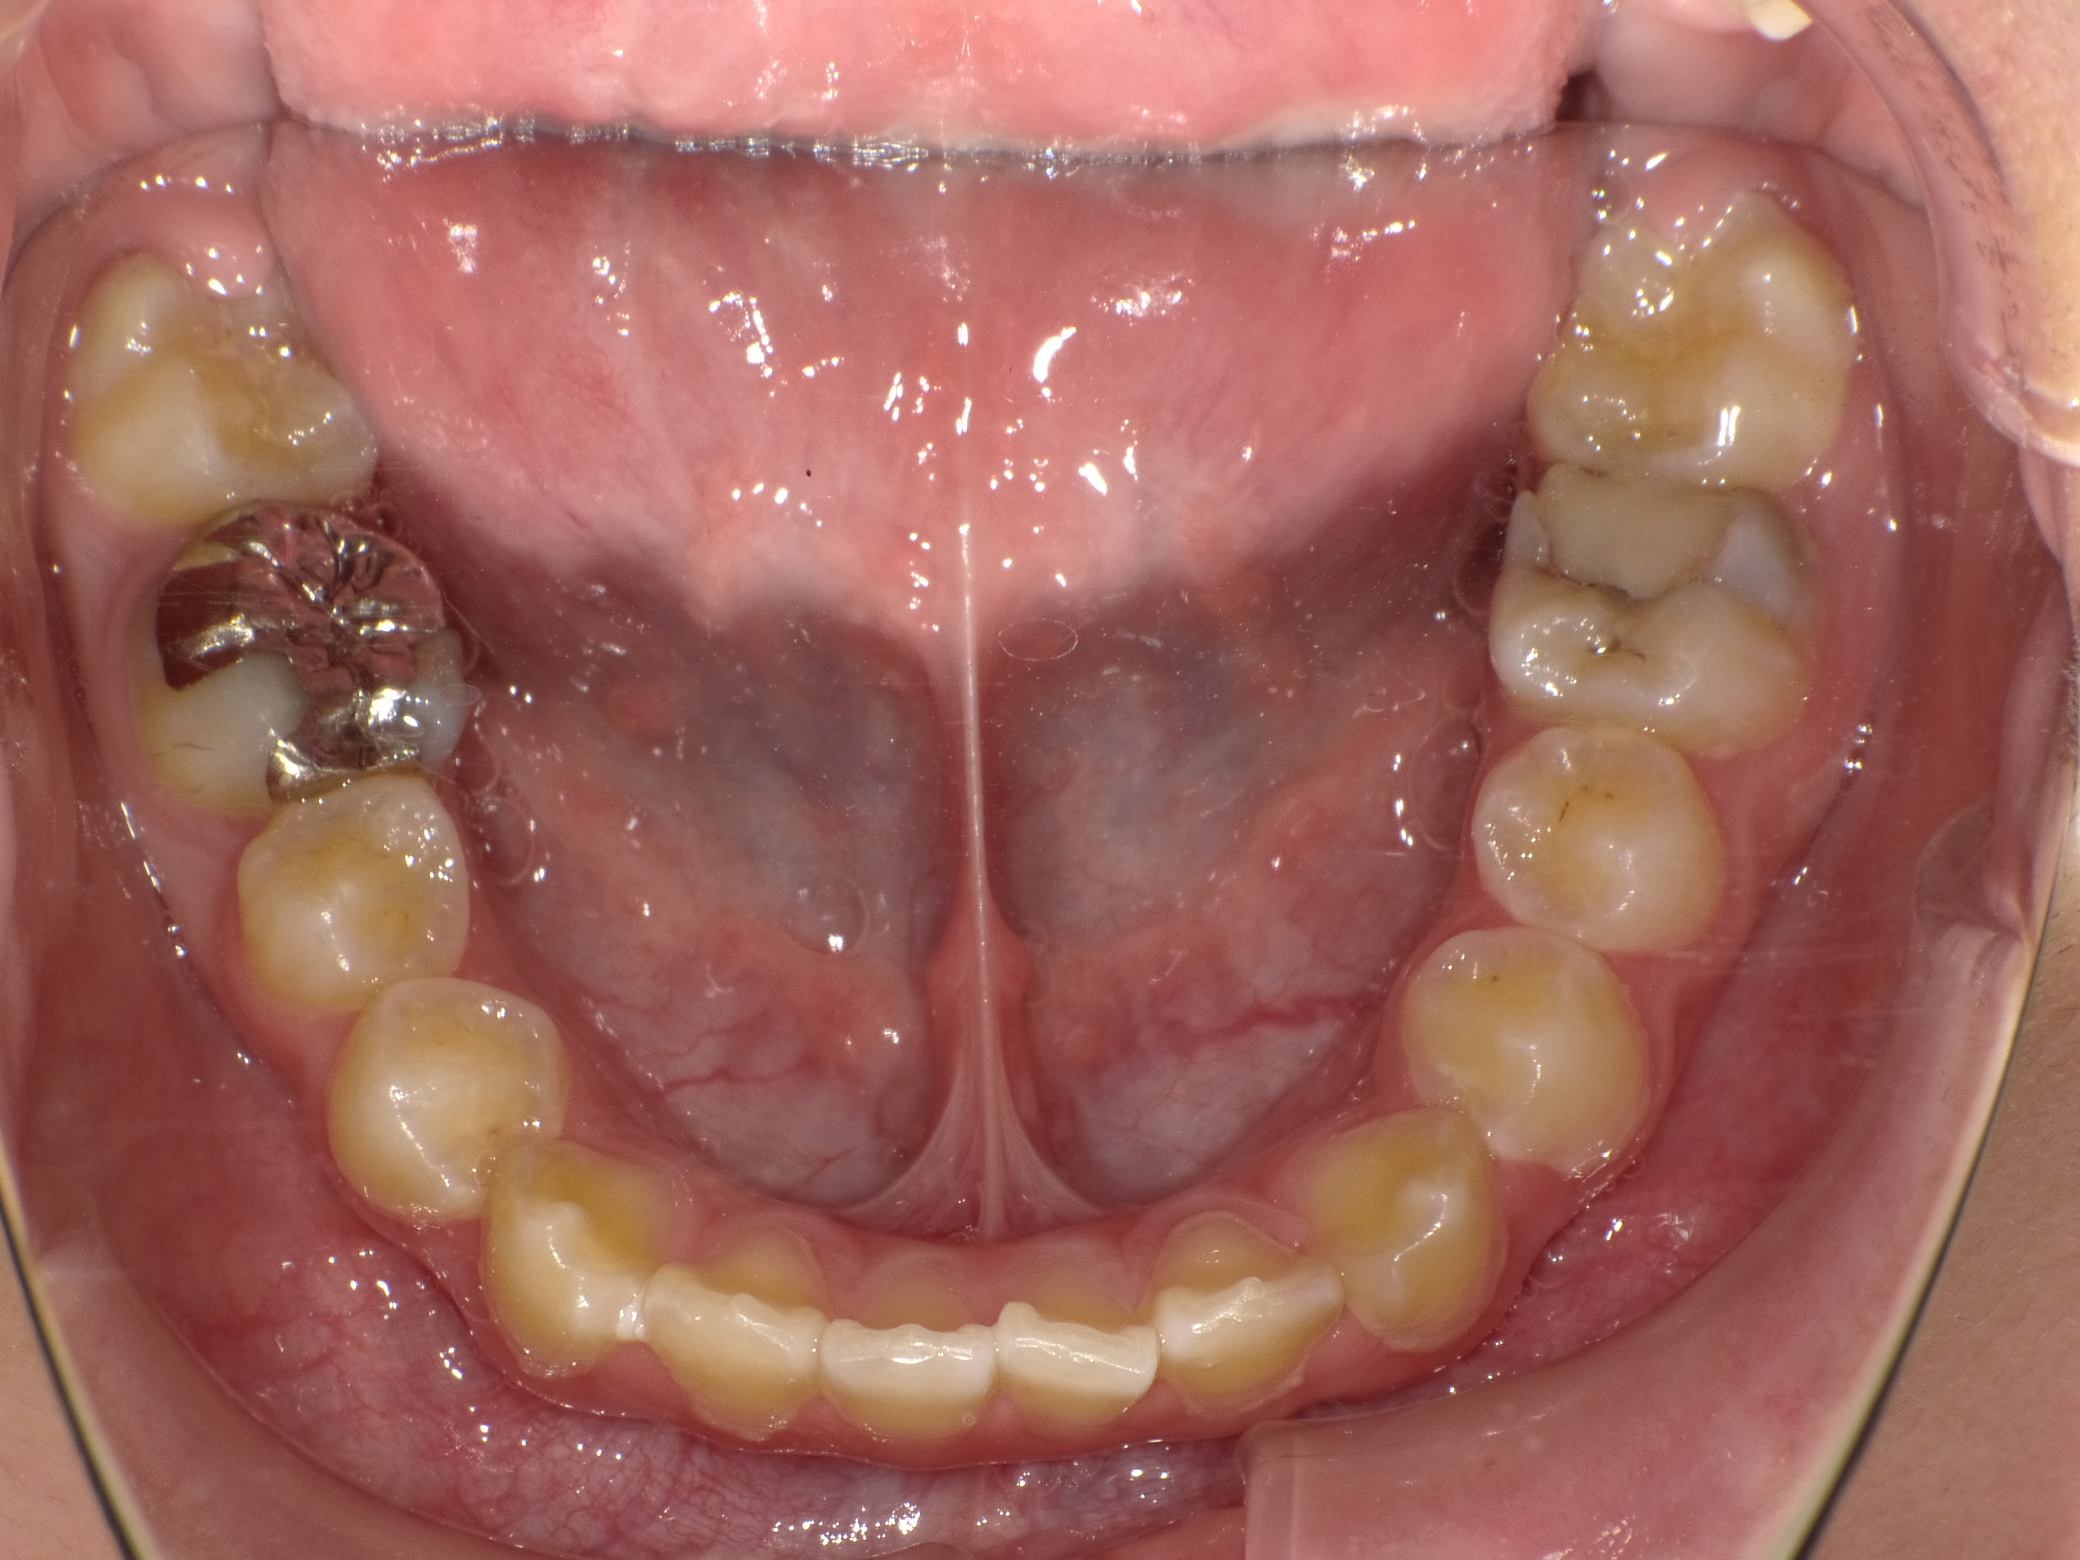

ドックスセメントを充填後です

経過を見たのち順次銀歯をはめていきました

自発痛などもなかったため経過は良好ですが、糖質制限や定期メンテナンスの継続が必須です